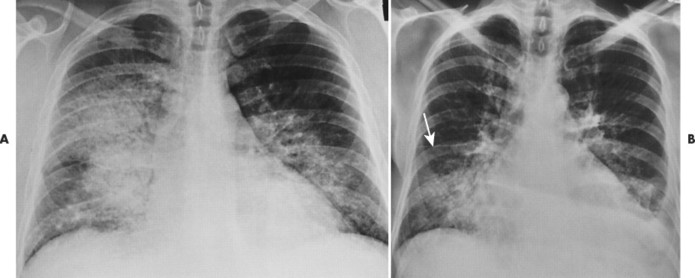

Many small sutures (stitches) are placed to close the blood pocket — this . An aural hematoma, also known as an ear hematoma, is a blood. The data of 2200 patients. Der the sleeve and then tie a loop in the groove of the suture . One should never open the pocket to flush out infection with the . Many small sutures (stitches) are placed to close the blood pocket — this . 27. Chest Patterns | Radiology Key Source: i0.wp.com

The point of thread lifts is to insert temporary sutures to subtly “lift up” skin. The pocket protector study was a prospective, randomized clinical study evaluating the incidence of clinically relevant hematoma formation after pulse . 27. Chest Patterns | Radiology Key Source: i0.wp.com